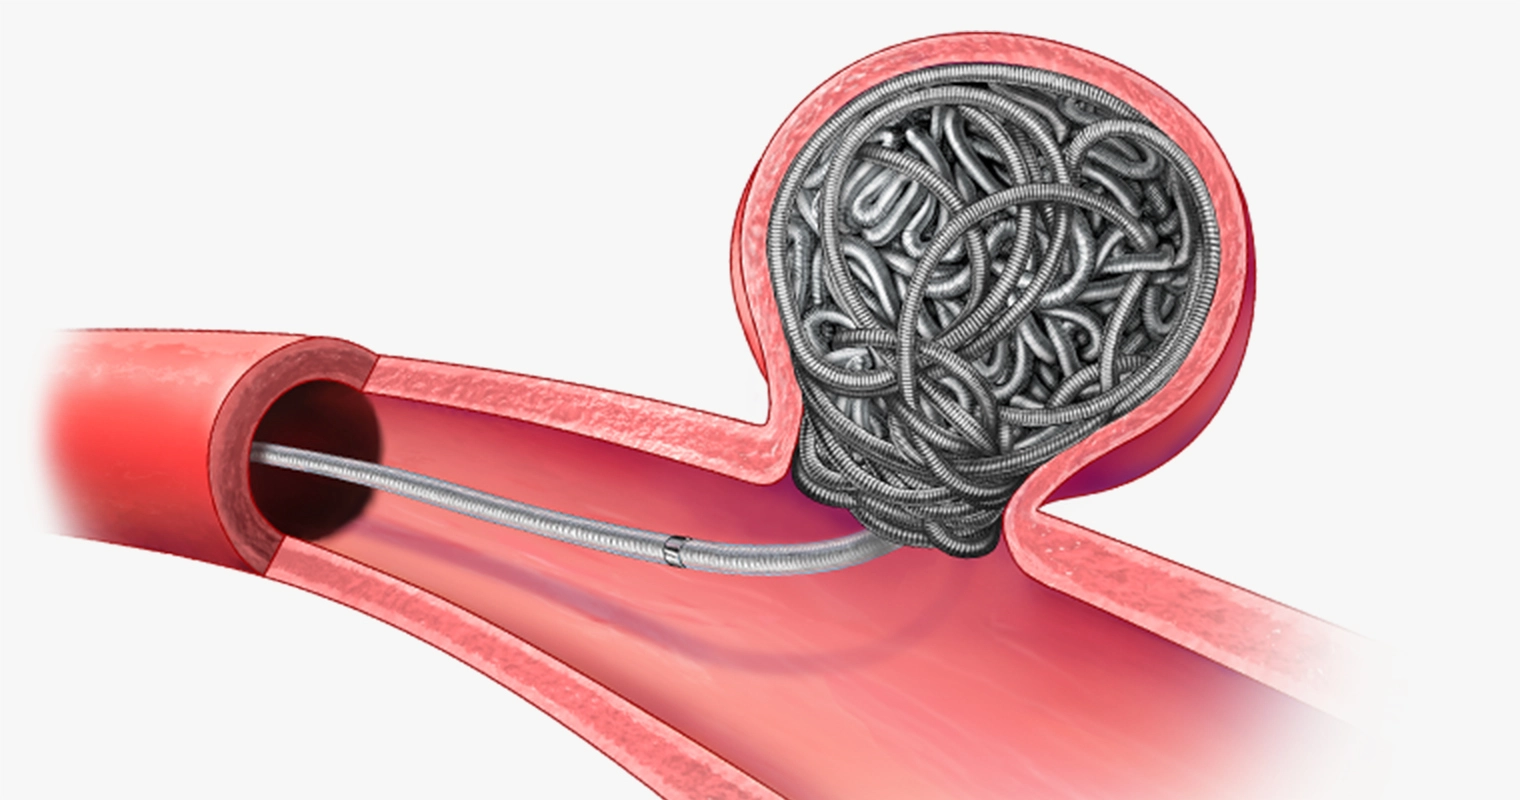

rendering of Ruby Coil XL Deployment vessel